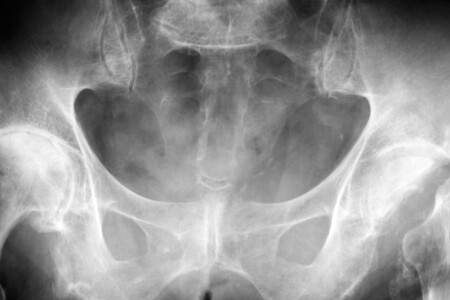

Zánětlivé onemocnění pánve (PID - pelvic inflammatory disease) je bakteriální infekce postihující vnitřní orgány ženského reprodukčního ústrojí - děložní sliznici, vejcovody (trubice, kterými se posunují vajíčka do dělohy) a vaječníky. Zánětlivé onemocnění pánve je často způsobeno infekcí, sexuálně přenosnou nemocí - například chlamydií nebo kapavkou, které se rozšíří na vnitřní reprodukční orgány. Nákazou jsou ohroženi především sexuálně aktivní dospívající dívky, které mají více sexuálních partnerů a praktikují nechráněný pohlavní styk.

Když bakterie proniknou děložním hrdlem a dostanou se do vnitřních reprodukčních orgánů, mohou způsobit zánětlivé onemocnění pánve. Infekce postihne děložní sliznici, vejcovody a vaječníky, projeví se zčervenáním, bolestí a zduřením. Může způsobit trvalou neprůchodnost vejcovodů, což brání oplodnění, nebo se oplodněné vajíčko nemůže dostat do dělohy a dochází k mimoděložnímu těhotenství, při kterém se vajíčko zachytí ve vejcovodu.

Má-li vaše dcera příznaky zánětlivého onemocnění pánve, je třeba co nejrychleji určit diagnózu a zahájit léčbu. Dětský lékař nebo gynekolog (specialista na léčbu poruch ženského reprodukčního ústrojí) provede pečlivě vyšetření pánve a nechá dívce udělat rozbory moči a krve, těhotenský test a kultivaci na kapavku a chlamydii. Obvykle je nutné také laparoskopické vyšetření (vyšetření dutiny břišní pomocí trubiček s optikou a kamerou, které se zavedou do břicha), kterým se zjišťují eventuální abscesy na vnitřních reprodukčních orgánech. Lékař zpravidla nechá dívce udělat testy na sexuálně přenosné choroby - například na syfilis, hepatitidu typu b a hiv.